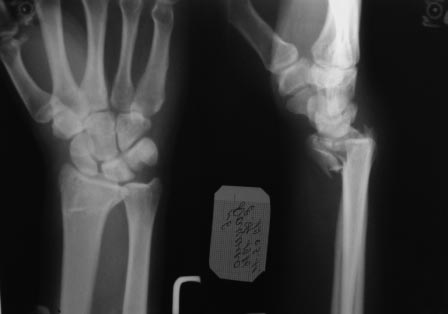

Но при повторной репозиции с экстензией кисти к тылу было отмечено недостаточное смыкание отломков суставной фасетки луча.

Учитывая,что при ЧКДО репозиция и удержание отломков происходит за счет лигаментотаксиса, мне более надежным показался вариант накостного остеосинтеза.

Накостный остеосинтез более стабильный в данном случае жэто верно, но и более травматичный, т.к. достоверно выставить фасетку луча можно только при артротомии и визуальным контролем, ЭОП не всегда дает объективную картинку, либо с помощью артроскопа. Артротомия негативно скажется на дальнейшей функции кистевого сустава. Аппаратный метод в случае внутрисуставного перелома минимизирует травму от лечения и даже в случае неполной репозиции суставной фасетки функция кистевого сустава на выходе будет лучше и восстановится значительно быстрее. Мое очень субъективное мнение что накостный остесинтез более адекватен при внесуставных переломов дистального эпиметафиза лучевой кости, когда репозиция не требует выполнения артротомии.